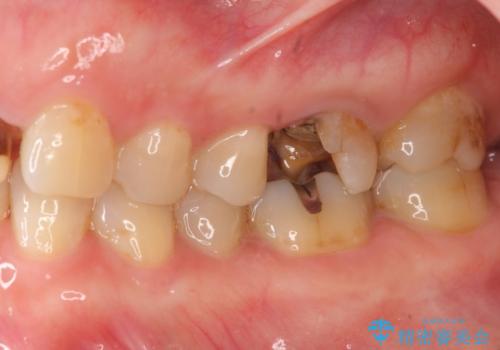

- 「 銀歯が原因で皮膚にアレルギー症状が出ている。」、と皮膚科のかかりつけ医に言われメタルフリー治療を希望され来院されました。

拡大鏡下で丁寧に銀歯の除去を行ったのち、金属を用いないセラミックインレー・クラウンによる治療を行います。